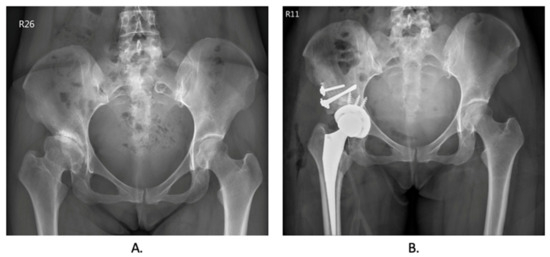

Before the total hip arthroplasty, the surgical plan was simulated for every patient, and the patient-specific instrument was printed for the surgery in Figure 2. Preoperative and postoperative X-ray images of the hip were collected and are included in Figure 3. Table 2 presents the peri-operative outcomes, including the mean and SD of several parameters. The average duration of the surgical procedure was found to be 221.17 min, with an SD of 19.65 min. The mean blood loss during the operation was 733.33 mL, with an SD of 355.90 mL. The mean length of hospital stay was calculated to be 6 days, with an SD of 0.89 days. Furthermore, the mean difference between the pre-and postoperative hemoglobin levels was 2.15, with an SD of 0.99. A total of three patients received 2 units of leukocyte-poor red blood cells (LPR) as an accepted blood transfusion. Notably, there were no reported complications observed after the operation. No implant loosening, stem sinking, graft loosening, or dislocation was found during the follow-up period.

Figure 2.

Representative radiographic image of preoperative and postoperative hip undergoing total hip arthroplasty. (A). Preoperative X-ray image of developmental dysplasia of the hip. (B). Postoperative X-ray image while undergoing total hip arthroplasty using patient-specific instrumentation.